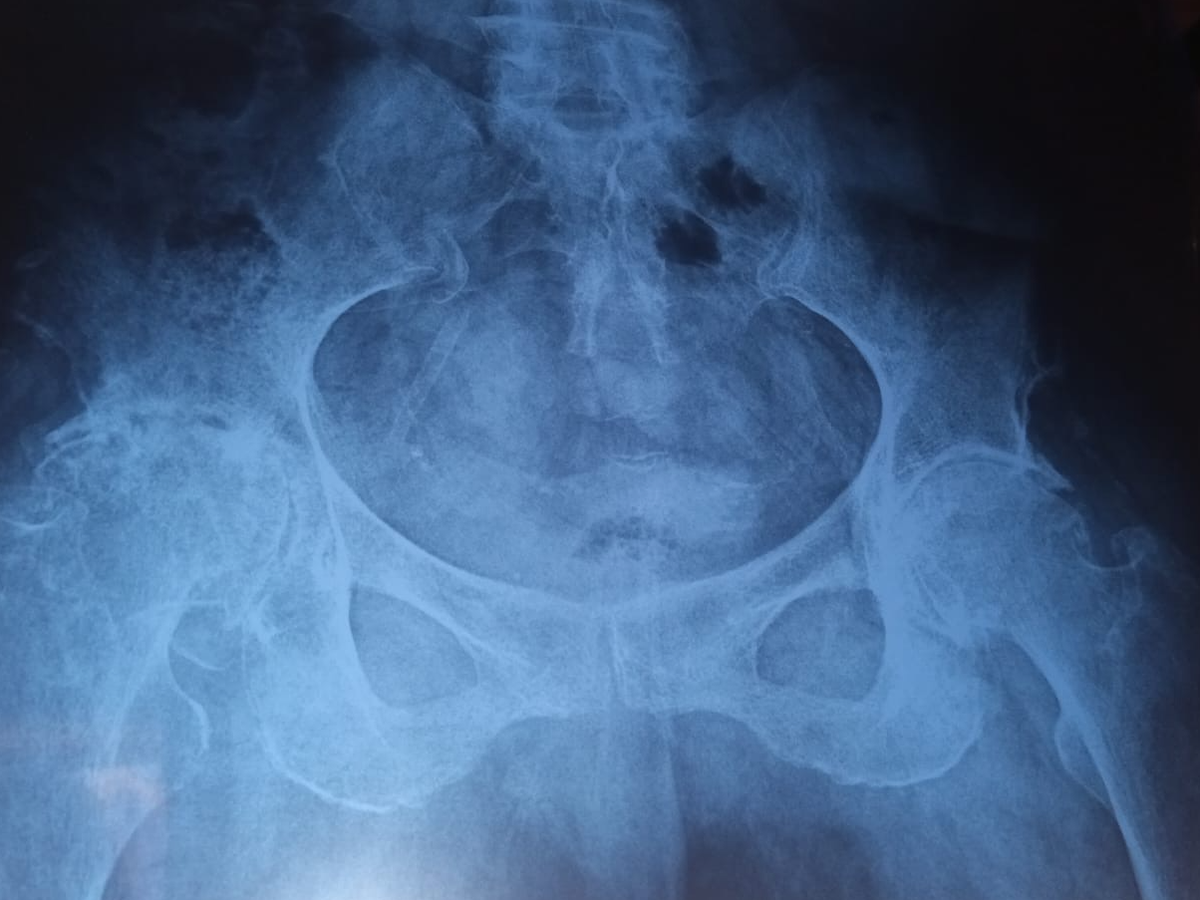

Necesita una cirugía de cadera y otra cirugía en ambas rodillas, ambas tienen un valor de $350,000.00 MXN más los gastos de consultas y medicamentos.